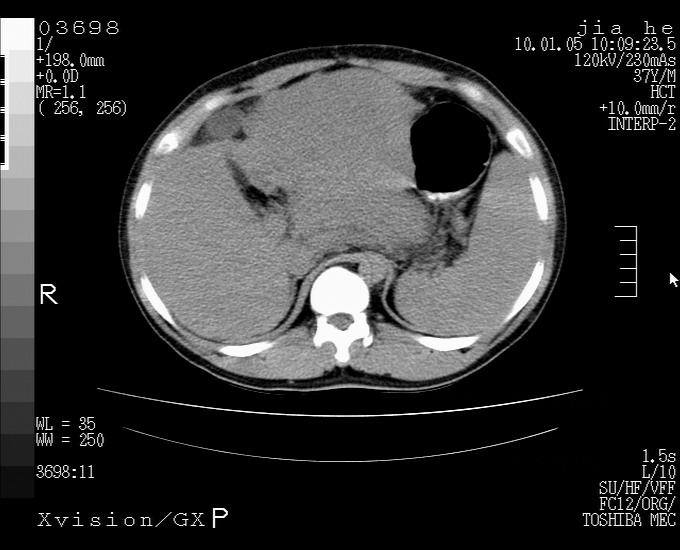

标题: CT23988:男,40岁,B超提示腹部肿物,请各位老师给看看。 [打印本页]

标题: CT23988:男,40岁,B超提示腹部肿物,请各位老师给看看。

3.肝左叶巨大站位,并腹腔淋巴结肿大,肝癌或肝间叶来源恶性肿瘤,也不排除大网膜间质瘤侵及肝左叶

肝硬化、脾大;胃底静脉曲张;是否门脉高压所致,建议进一步检查。

还有个异位胆囊。临床资料太少,肿瘤、左叶发育异常、肝硬化。不过看密度是个低密度为主的,新生物倾向于第一位。强化吧!